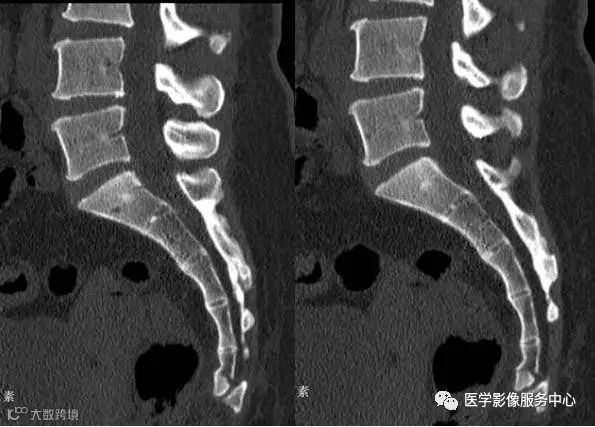

病人女性,外伤后骶尾部疼痛,dr片示骶尾关节对应关系差,骶5椎体欠规则。ct重建示骶5椎体粉碎性骨折!

CT